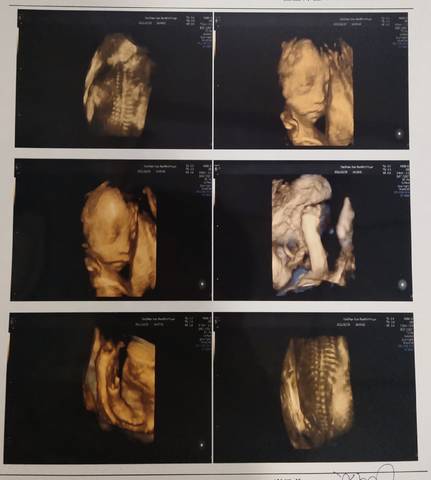

请大家帮我看看是男孩是女孩

大方的旅人 2022-01-01 11:51

你好亲爱的,通过这个来判断男孩女孩是不太准确的哈,我们要给他同等的关爱和呵护,也祝你可以如愿以偿,心想事成。

你好。我们是判断不了男宝宝跟女宝宝的,孕期定期检查,我觉得宝宝健康就好的。祝心想事成 。

可爱的孕妈,我们都是一样觉得好奇,这个确实没啥依据可参考的,就算B超有图片也只是一个宝宝的轮廓,祝您如愿!

看不出来,这个普通人是很难直接判断男孩还是女孩的哦,其实只要孩子健健康康就好,生下来才最准